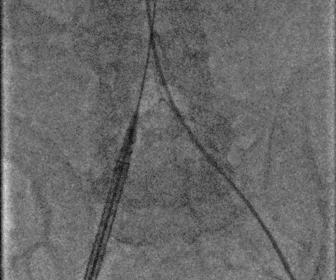

股动脉造影

图片

18f鞘芯预扩张